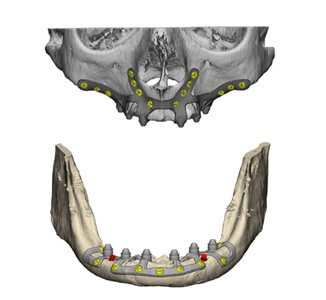

La introducción de la tecnología digital en odontología ha representado un avance significativo en nuestra práctica, y particularmente valioso en la optimización del tiempo de tratamiento, transformando la forma en que llevamos a cabo diversos procedimientos. A través de la tomografía computarizada de haz cónico (CBCT) y modelos 3D intraorales obtenidos mediante escáner intraoral, se recopila la información para que los softwares conozcan las dimensiones reales del paciente y puedan diseñar una estructura que se ancle al hueso remanente y, a su vez, pueda sostener prótesis fijas en rehabilitaciones parciales o totales. Estos implantes se fabrican con modelos hechos con impresoras 3D y sinterización láser directa de Titanio (DMLS), simplificando y optimizando nuestras prácticas.

- Solución a medida: Diseñados y fabricados con tecnología 3D para adaptarse a la anatomía ósea del paciente, permitiendo una mayor precisión y ajuste.